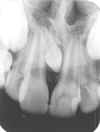

ANOMALIAS

1